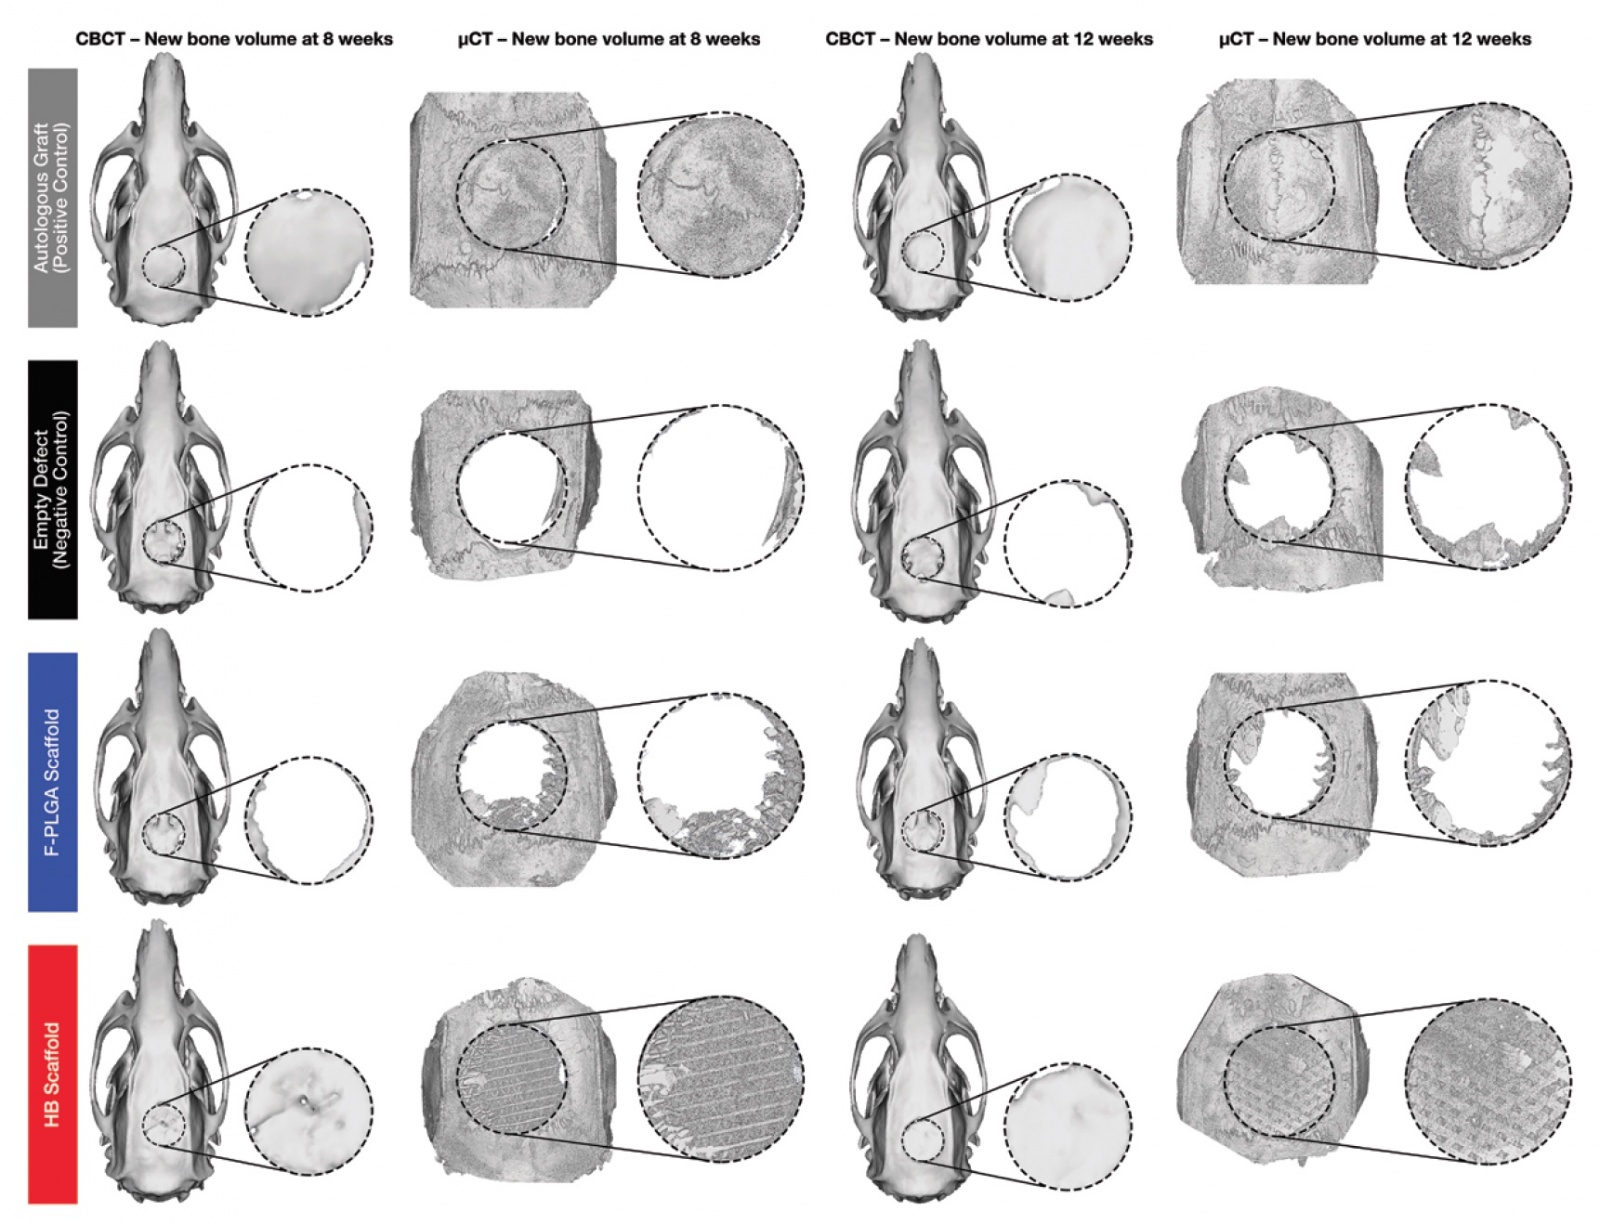

Изображение №3а: серый — с аутологичной костью; черный — без имплантата; синий — с имплантатом из поли (молочно-гликолевой кислоты); красный — с гиперэластичной костью.

На изображении выше (3а) представлены трехмерные реконструкции конусно-лучевой и микро-компьютерной томографий. Количество регенерированной костной ткани определяли по количеству минерализованной кости как доли от общего объема ткани, представляющего интерес. Объем кости на долю общего объема для гиперэластичной кости, поли (молочно-гликолевой кислоты) и для отрицательно-контрольной группы были нормализованы относительно объема кости на долю общего объема для положительно-контрольной группы (с аутологичной костью). Таким образом проводился сравнительный анализ показателей эффективности работы всех вариантов имплантата.

Конусно-лучевая и микро-компьютерная томографии показали увеличение количества минерализованного костного матрикса в дефектах, обработанных гиперэластичными костными имплантами (3b).

По данным конусно-лучевой томографии объем минерализованной кости в случае применения гиперэластичного костного имплантата составил 55,7% на 8 неделе и 57,0% на 12 неделе наблюдений. По данным микро-компьютерной томографии — 36,1% на 8 неделе и 37,1% на 12 неделе наблюдений. Это данные до нормализации.

После была проведена нормализация к показателям объема минерализованной кости в случае аутологичных трансплантатов. Теперь стало видно, что объем регенерации с применением гиперэластичной кости составил 95,6% и 82,0% (8-ая и 12-ая неделя наблюдений) от объема положительно-контрольной группы (с аутологичной костью). А микро-компьютерная томография дала следующие результаты: 74.2% и 64.5% (8-ая и 12-ая неделя наблюдений).

Применение исключительно поли (молочно-гликолевой кислоты) в качестве материала для имплантации оказалось достаточно неэффективным: 16.6% и 22.5% (8-ая и 12-ая неделя наблюдений) от объема положительно-контрольной группы. Малоэффективность этого метода подтверждается еще и тем, что его результаты не сильно отличаются от результатов отрицательно-контрольной группы, у которой вообще не было имплантатов: 10.3% и 13.8% на конусно-лучевой томографии и 14.5% и 19.5% на микро-компьютерной томографии.

Сравнение результатов испытываемого нового материала (гиперэластичной кости) с результатами отрицательно-контрольной группы показало разницу в объеме минерализованной кости в 7,81 раза на 8 неделе и в 5,75 раза на 12 неделе в пользу гиперэластичной кости.

Таким образом, с точки зрения объема регенерации применение гиперэластичной кости практически сопоставимо с применением коммерческих вариантов имплантатов с аутологичной костью.